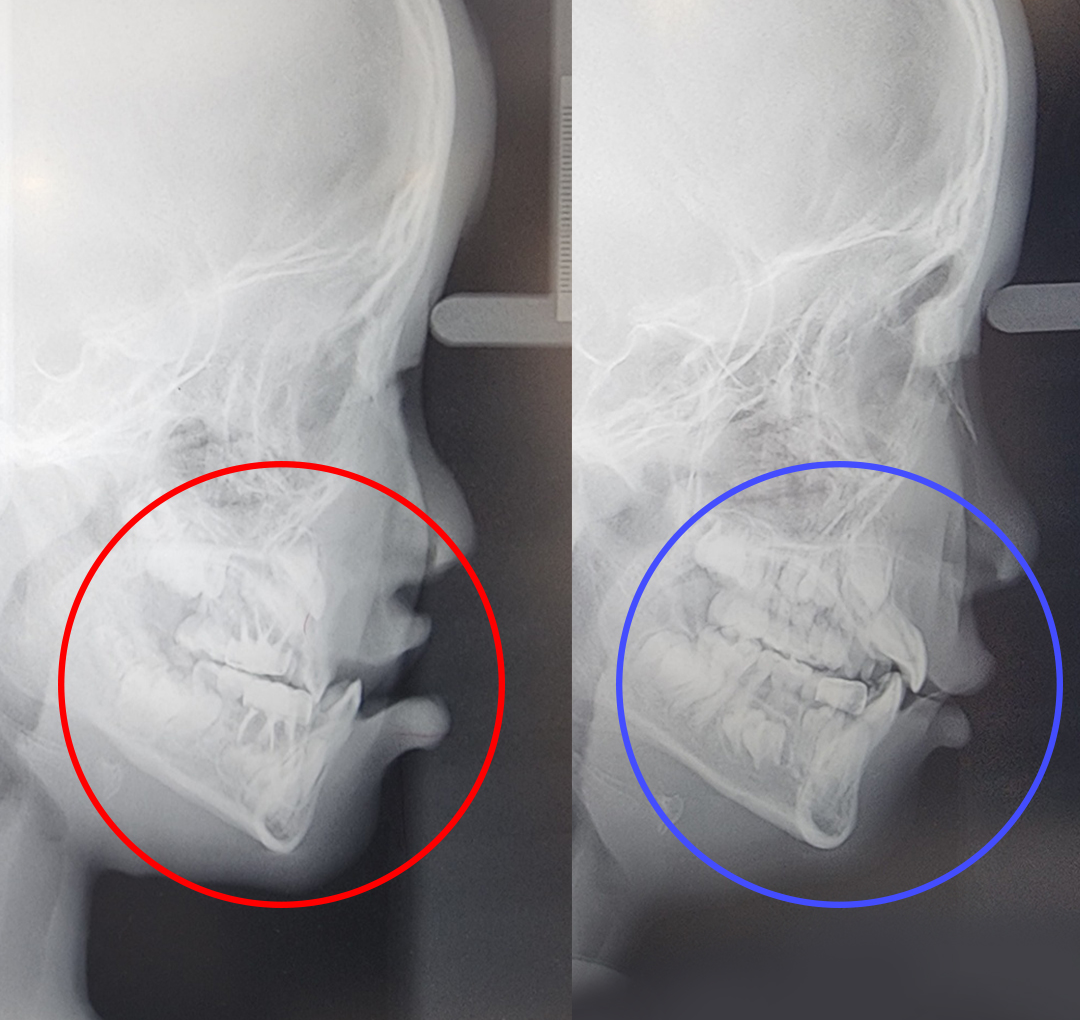

프랑켈장치 교정

어린이 3급 부정교합 & 프랑켈장치 교정

구호흡을 지속적으로 하게 되면 아래턱이 하방 성장하면서 아래 앞니가 위 앞니를 덮는 부정교합이 될 수 있습니다.

프랑켈장치 교정.

어린이의 치아와 턱뼈를 정상 위치에서 정상적으로 성장할 수 있도록 도와주는 치료 방법입니다. 프랑켈장치 교정은 영구치가 나오기 전, 유치 때부터 일찍 치료하여 편하게 정상교합이 될 수 있습니다. 프랑켈장치 교정은 만 3~12세에 가능하지만 만 4~6세에 치료를 시작하면 좋습니다.

- 5주걱턱과 양악수술을 예방할 수 있습니다.